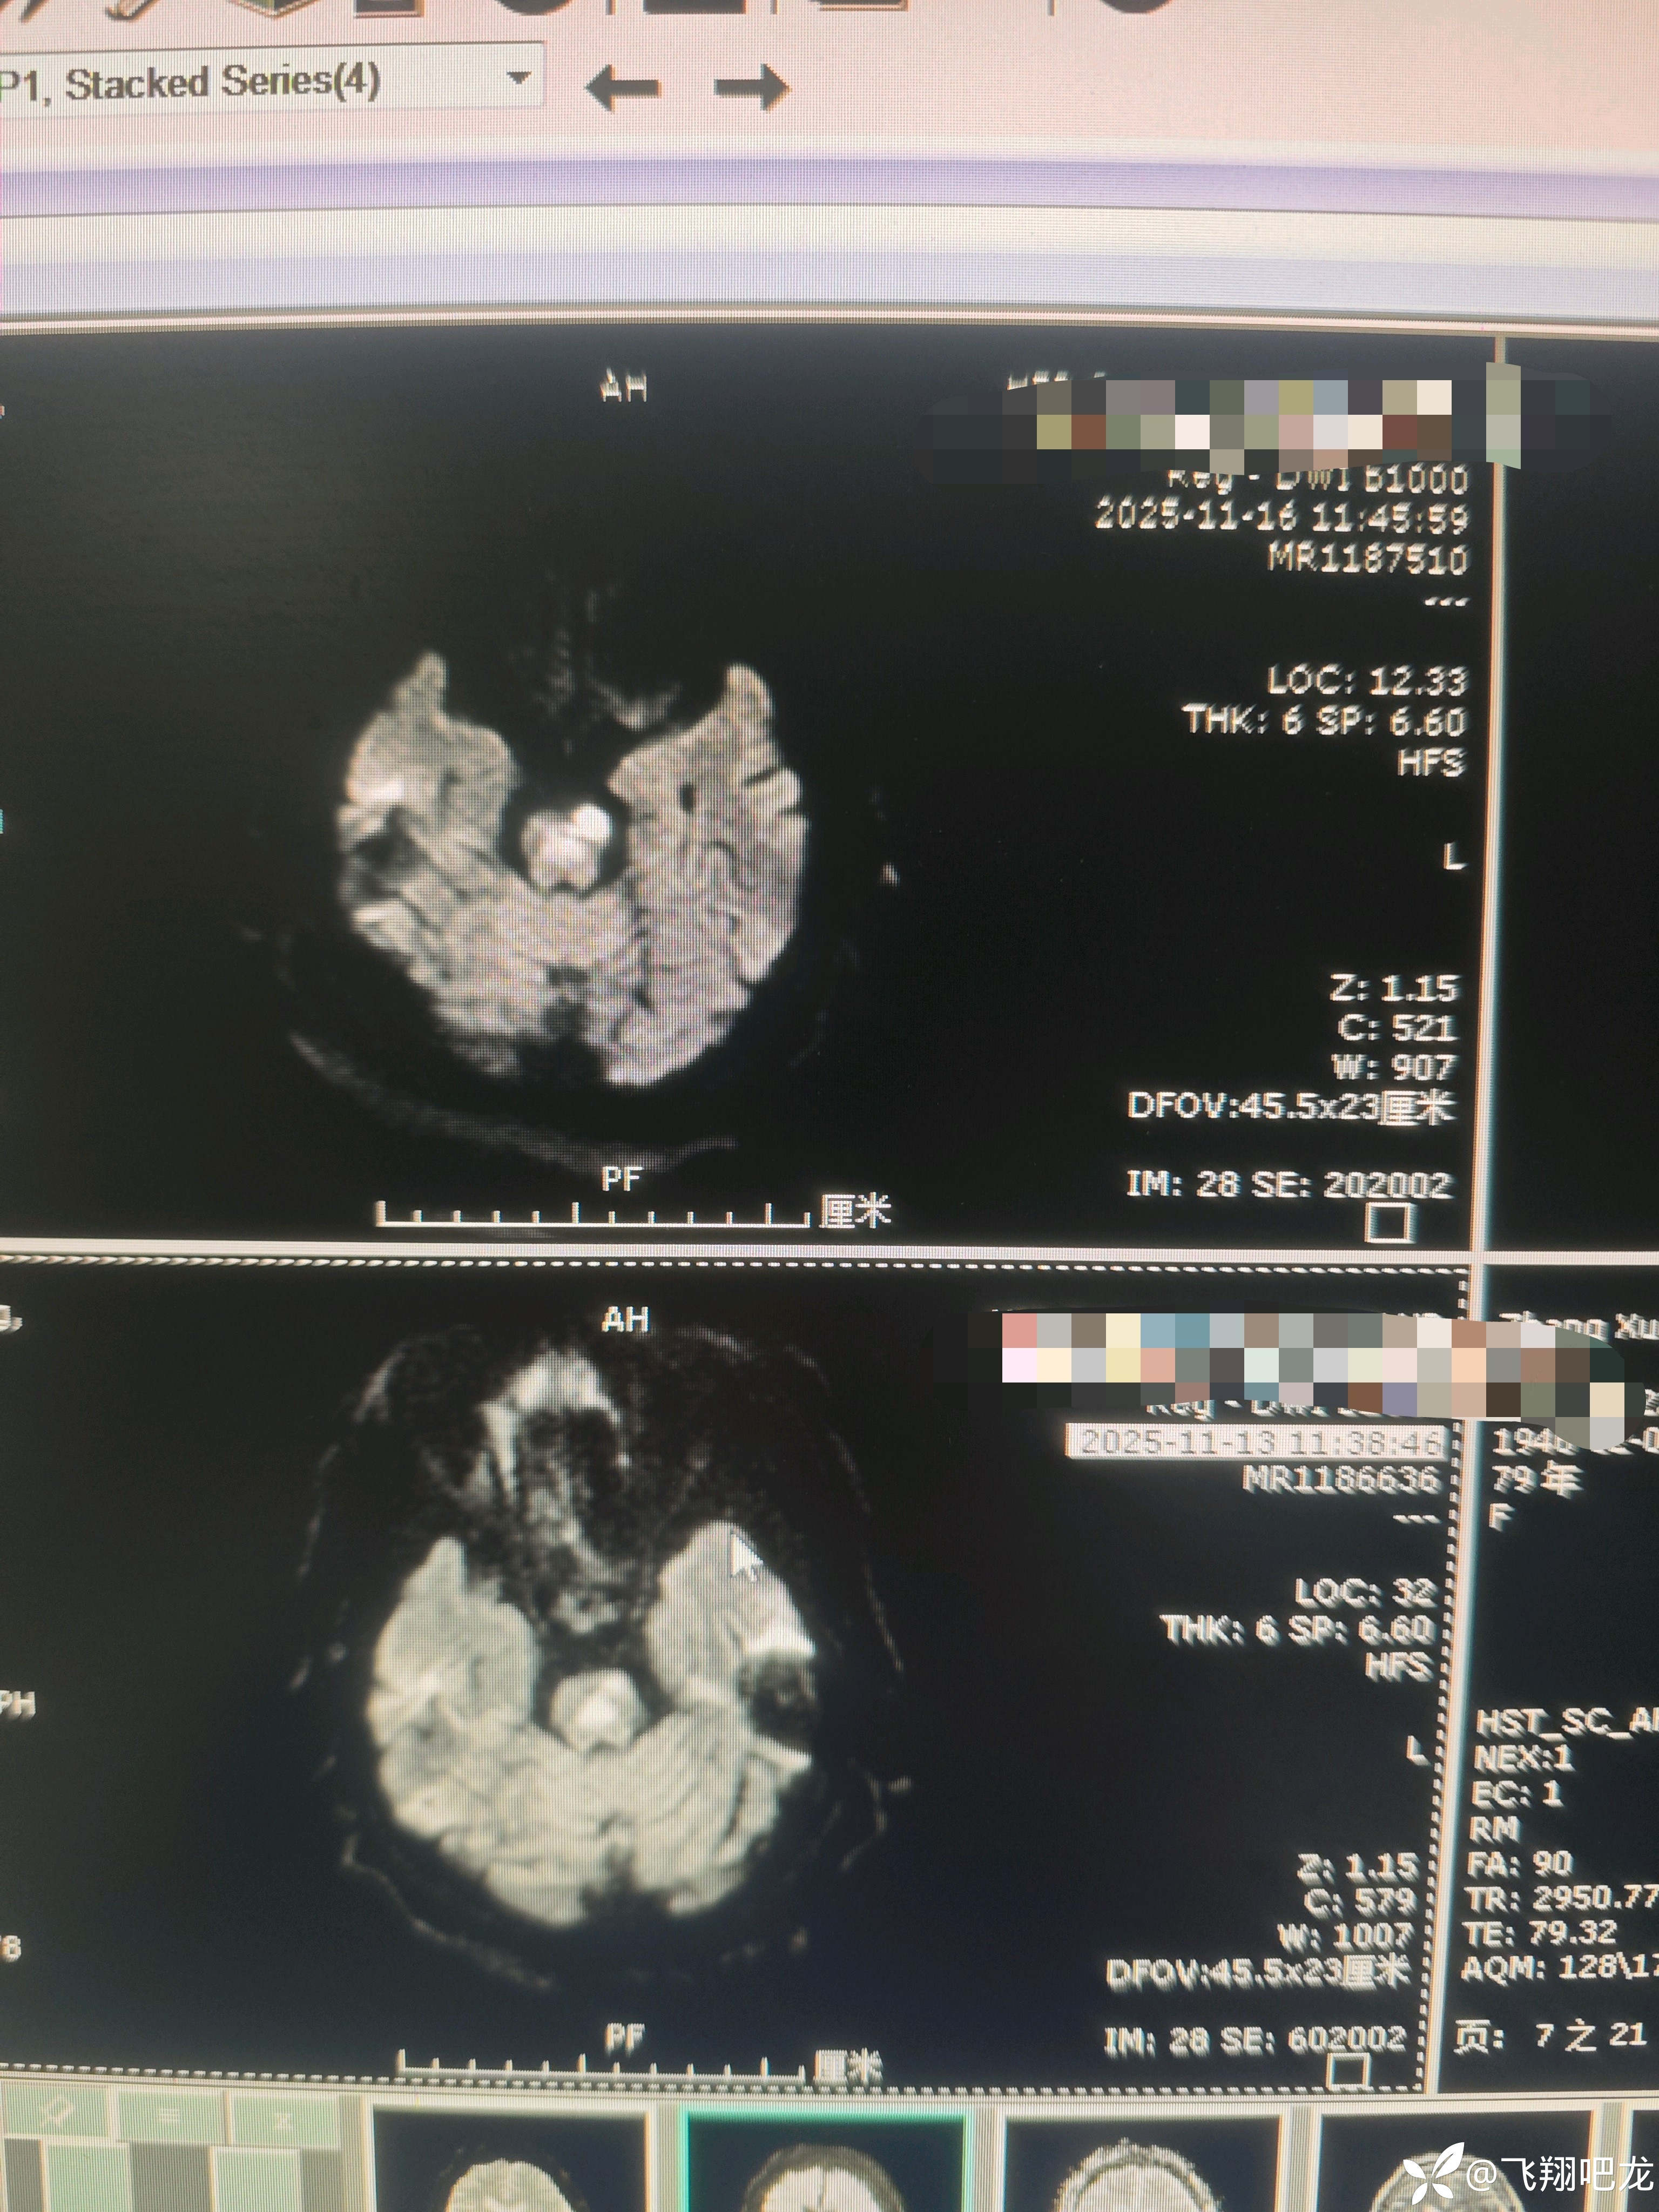

患者老年女性主因是脑梗死住院,入院后治疗期间再发意识不清。查核磁梗死面积加重。